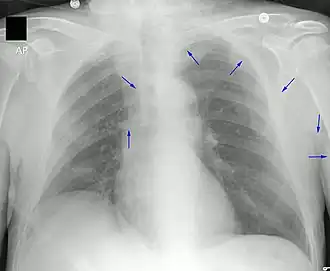

Chest X-ray showing tip of PICC line in the superior vena cava. Arrows provided to highlight the PICC line.

A PICC is inserted in a peripheral vein such as the cephalic vein, basilic vein or brachial vein in the arm, and then threaded through the veins toward the heart, until the end of the catheter rests in the proximal superior vena cava or cavoatrial junction. They must be inserted by a trained medical professional, including a physician, but also any trained medical professional such as a specially trained registered nurse.[8] and Interventional Radiology Technogists.[6][12] An ultrasound or chest X-ray, the use of fluoroscopy, or electrocardiography navigation can be used during insertion and to confirm placement. The insertion is a sterile procedure, but does not need to be performed in a completely sterile environment like an operating room.